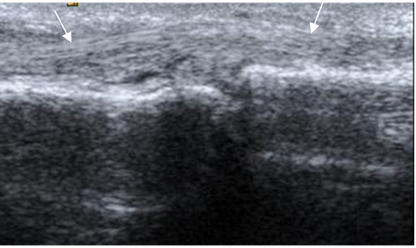

Los tendones del mecanismo flexor y extensor, se aprecian como estructuras hipoecoicas y con distribución fibrilar en la ecografía. (Fig 28).

Fig 28. Mecanismo extensor.

Ecografía sagital. Tendón extensor normal.